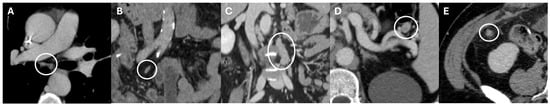

| Loch et al. [20] | Retrospective | CT | 91/443 | Gastric adenocarcinoma |

|

| Jiang et al. [21] | Retrospective | CT | 376/605 | Gastric cancer |